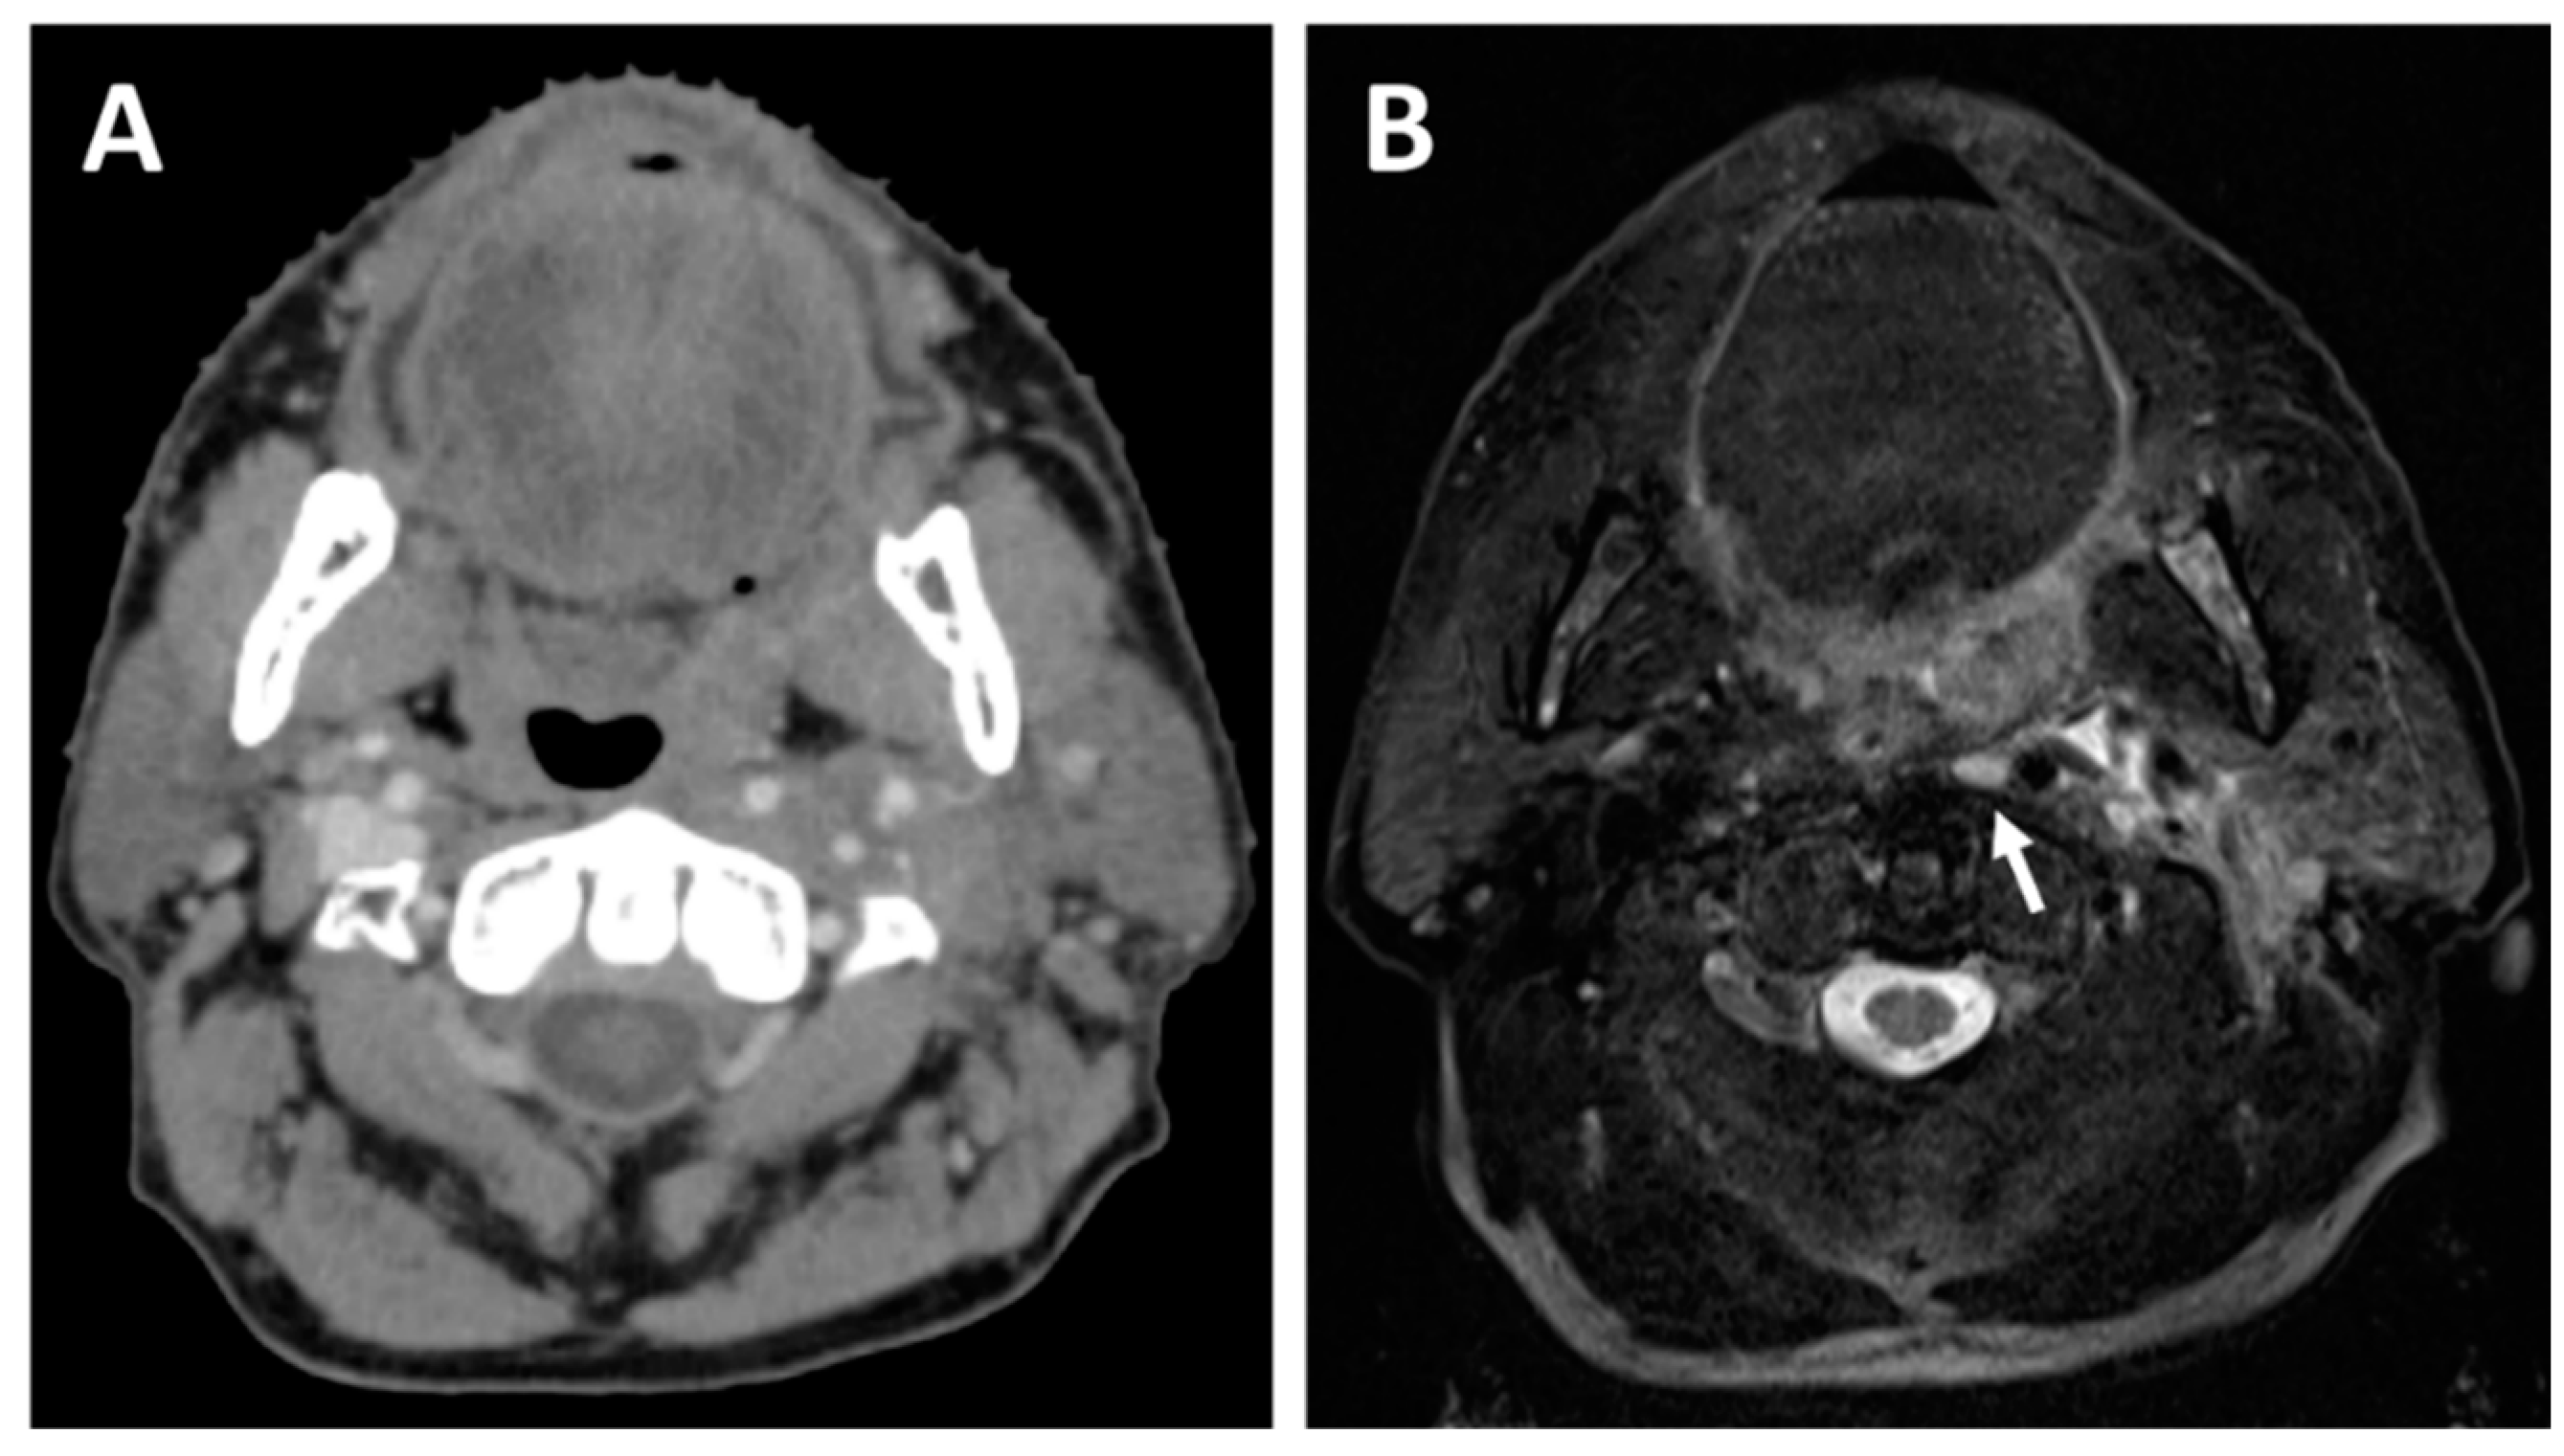

2.2. Lymph Node Evaluation

2.3. Treatment Planning